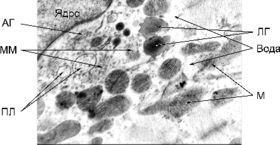

При вивченні ультратонких зрізів тканини міокарда були виявлені наступні зміни (див. рис. 1).

Мітохондрії кардіоміоцитів з дещо підвищеною електронною щільністю, дезорганізовані, а саме, розпушені кристи внутрішньої мембрани. Частина мітохондрій містить значні ділянки електронно-світлих гомогенних мас. Саркоплазма має знижену електронну щільність внаслідок підвищеного вмісту рідини. Кількість рибосом та полісом знижена, у значній кількості наявні краплі ліпопротеїдів низької щільності. У саркомерах міофібрил Z-смуги не чіткі, а також порушена структурна орієнтація волокон актину та міозину. Сарколема, переважно, згладжена, а в окремих ділянках її електронна щільність підвищена. Каріотека ядер кардіоміоцитів на більшості ділянок дезорганізована, особливо тих, що прилягають до гіпертрофованого апарату Гольджі. Останній містить збільшену кількість розширених цистерн, мікроміхурців, первинних лізосом, мультивезикулярних тілець.

Рис. 1. Будова кардіоміоцита у морських свинок за умов гострої сироваткової хвороби (набряк мітохондрій та саркоплазми, релаксовані міофібрили): М – мітохондрії; ПЛ – первинні лізосоми; АГ – апарат Гольджі; ЛГ – ліпопротеїнові гранули; ММ – мікроміхурці; Зб. – Ч 21000